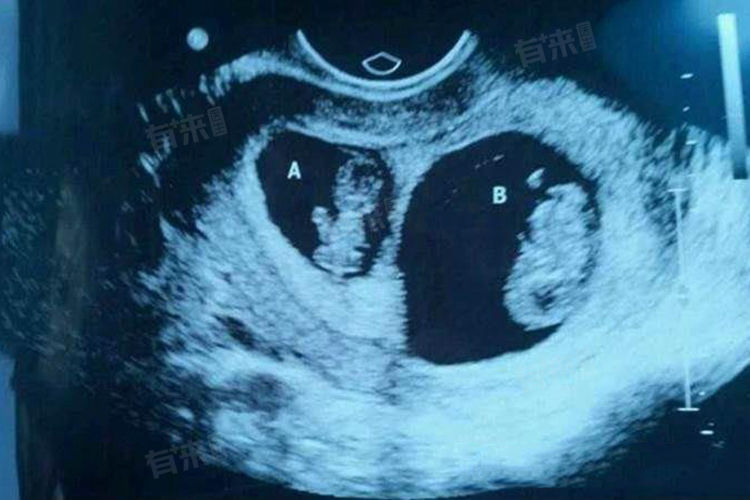

双胞胎的形成可以由多种因素造成,主要包括遗传因素、药物因素、辅助生殖技术以及非医源性因素等。

双胞胎的形成是一个复杂的过程,涉及多种因素的相互作用。遗传因素、药物因素、辅助生殖技术以及自然因素等都可能对双胞胎的形成产生影响。因此,对于想要生育双胞胎的夫妻来说,应该充分了解这些因素并咨询专业医生的意见。同时,在怀孕期间也应该注意保持良好的生活习惯和饮食习惯,以确保母婴的健康和安全。